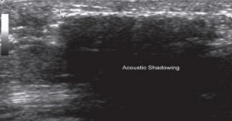

Clean shadowing

Caused by attenuation of an object

Ex: stones, metals, bone, needle

Dirty shadowing

Caused by refracting properties of gas bubbles or impedance of gas